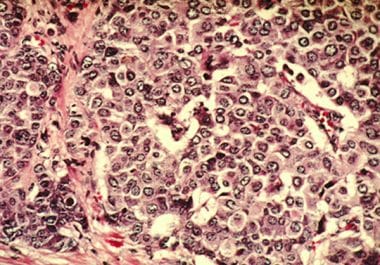

The FDA approved a kinase inhibitor for the treatment of inflammatory myofibroblastic tumors in children and adults. The U.S....